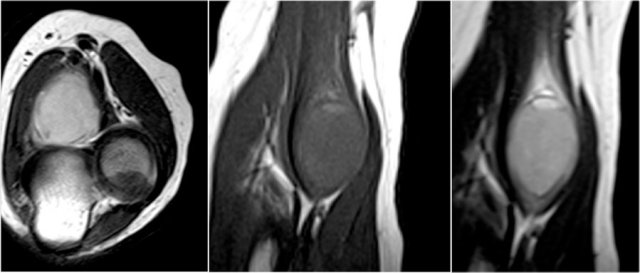

Radiobicipital bursitis

Here are sagittal and axial images of a patient who was referred to an orthopedic oncology surgeon for a mass near the elbow.

There is a partial tear (arrow) of the biceps tendon, but the question is, what is the structure that we are looking at and what is within it.

The structure is the radiobicipital bursa, so this is a bursitis.

Remember that the biceps tendon does not have a tendon sheaht, so tenosynovitis is not a possibility.

The differential diagnosis for the low intensity structures within the bursa is: synovial chondromatosis, PVNS and rice bodies.

It turned out to be rice bodies.

In any synovial lined joint or bursa these rice bodies can be formed as a result of chronic inflammation with synovial hypertrophy.

The villi will outgrow their blood supply, become necrotic and fall into the joint or bursa.

They are called rice bodies because when you open up the joint, they just look like rice.

Here another case.

The white arrow in the left sided image is pointing to the bursa.

Notice that the biceps is intact.

Next to the radiobicipital bursa (yellow arrow), also an interosseous bursa (red arrow) was described by Abdalla Skaf in Radiology in the article entitled: Bicipitoradial Bursitis: MR Imaging Findings.

Sometimes these masses mimic a tumor or they can cause impingement on the radial nerve when they become very large.